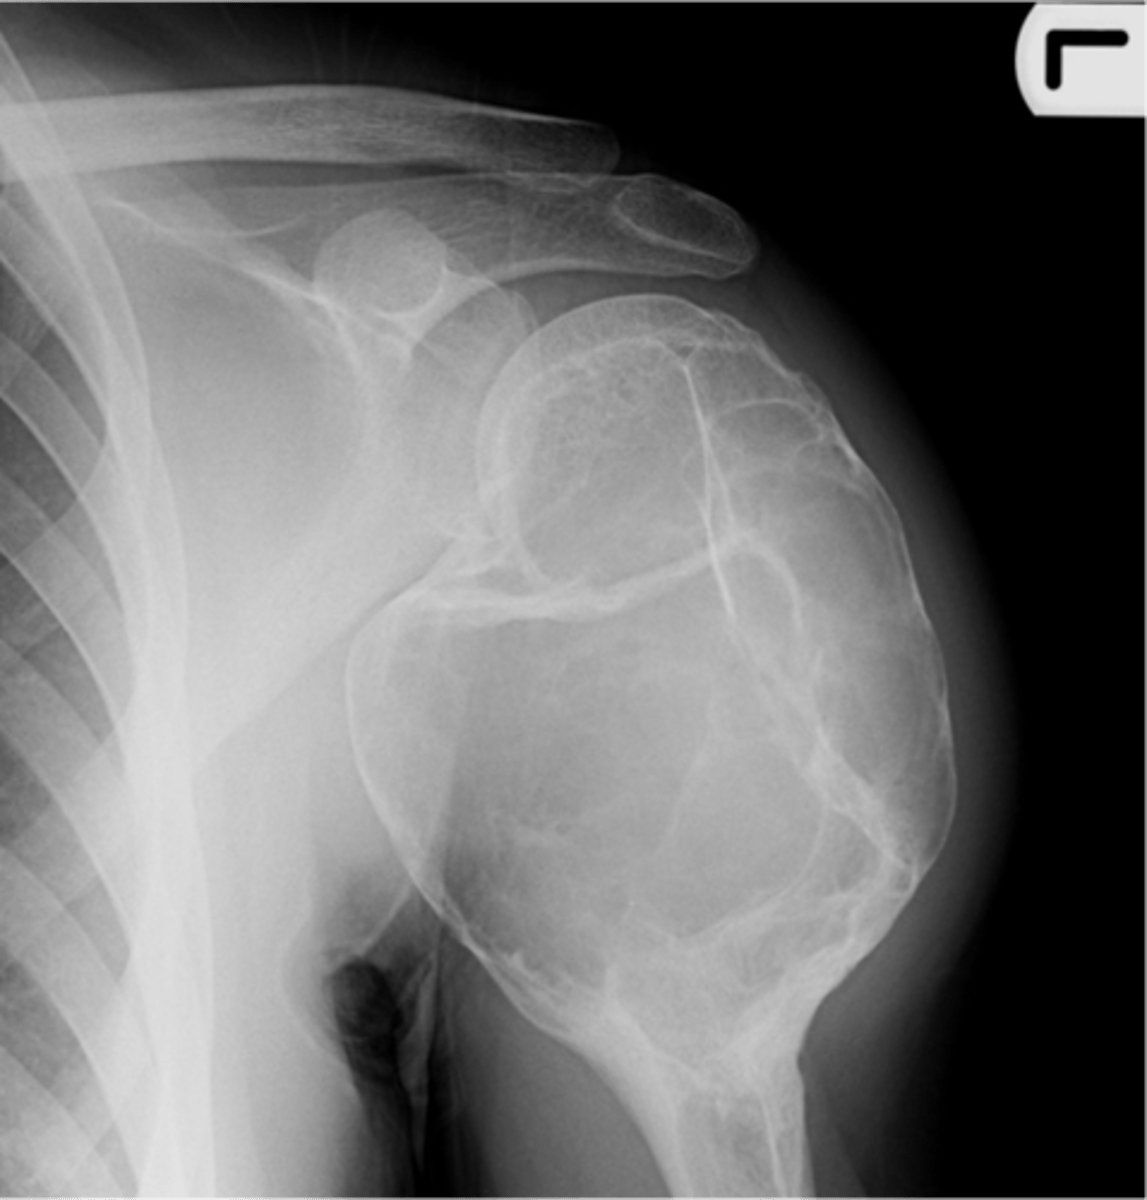

Osteoblastoma

- 10-20 y.o. (3-78 y.o. reported)

- M:F, 2:1

- Spine

• Painful scoliosis

• Posterior elements

- Femur, foot, ankle

• Nidus >2cm

<p>- 10-20 y.o. (3-78 y.o. reported)</p><p>- M:F, 2:1</p><p>- Spine</p><p>• Painful scoliosis</p><p>• Posterior elements</p><p>- Femur, foot, ankle</p><p>• Nidus &gt;2cm</p>